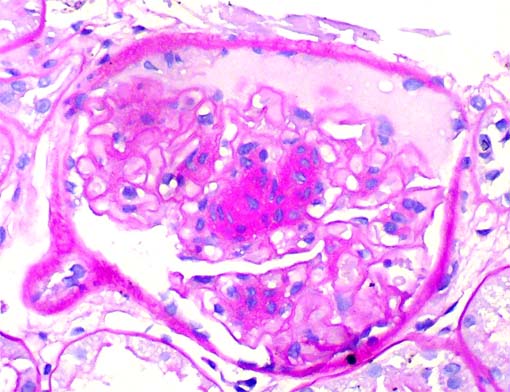

Figura 8.

PAS, X400.